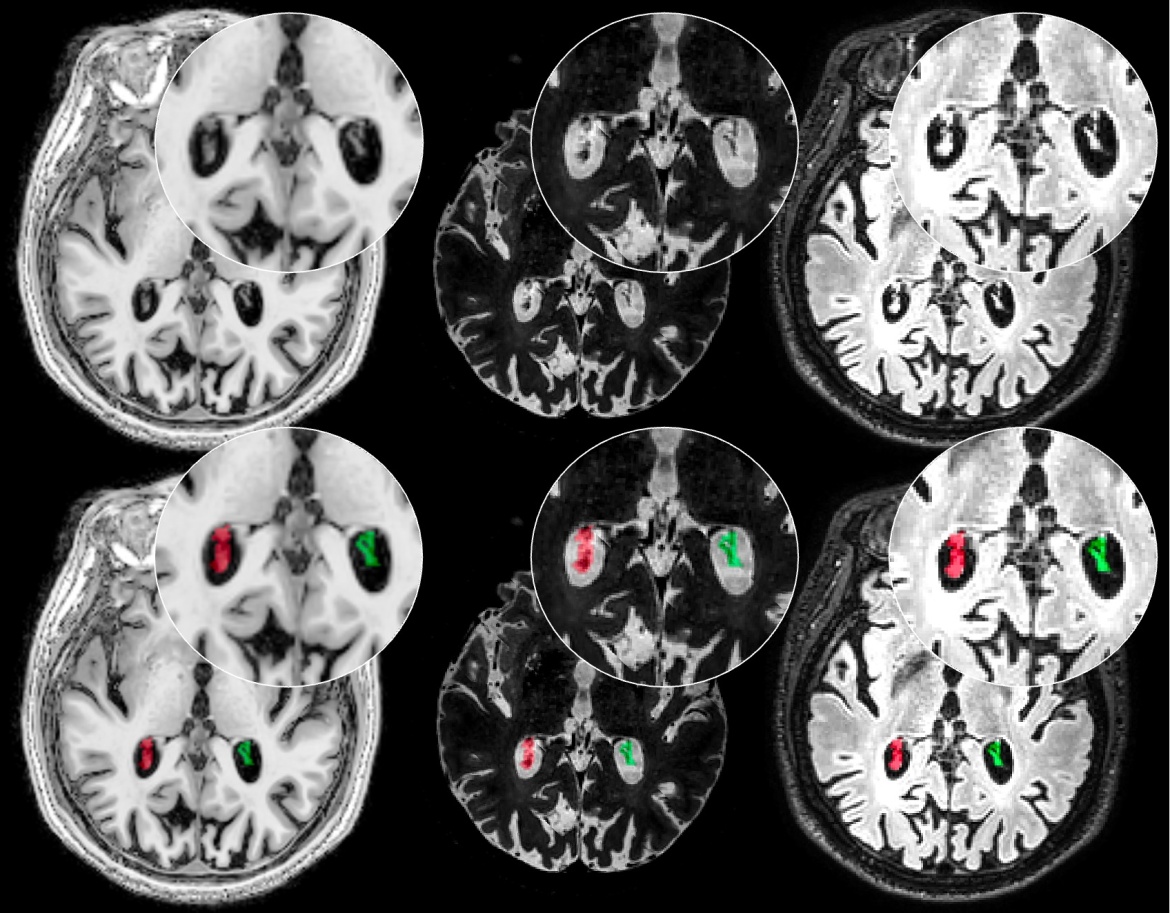

Flow Territory Map Atlas

flow territoriesFlow territory map atlas developed by Dr. Manus Donahue. A flow territory probability atlas of left and right internal carotid artery (ICA) and vertebrobasilar artery flow territories calculated from 158 subjects using vessel-encoded pseudocontinuous arterial spin labeling (VE-pCASL). The atlas is in 2 mm Montreal Neurological Institute Space.